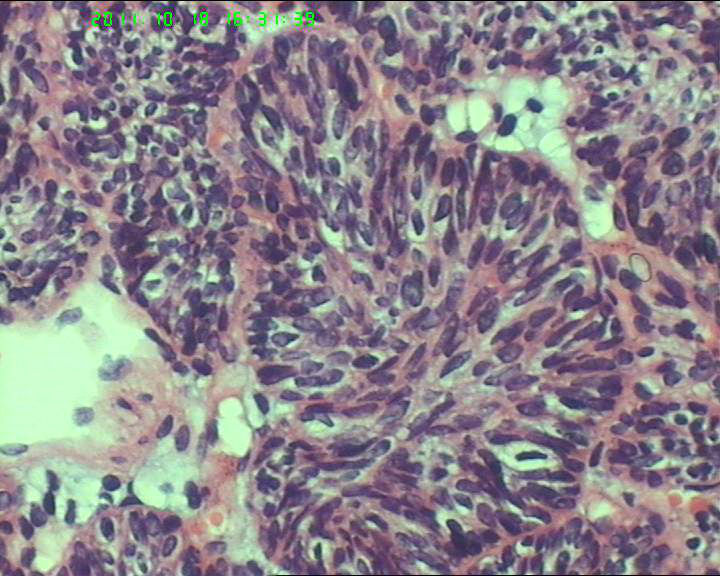

70岁女性体检发现膀胱肿物,是癌吗?

膀胱后壁一2*1cm大小肿物